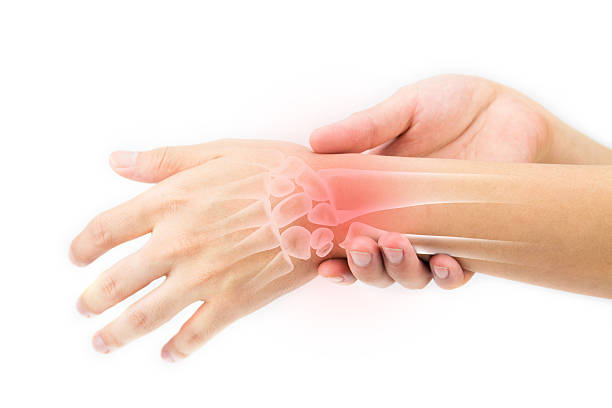

6. 류마티스 관절염 초기증상 – 부종

류마티스 관절염 초기증상 여섯 번째는 부종입니다. 평소와 다르게 신체 여러부위에서 붓는 느낌이 든다면 이 때에도 류마티스 관절염일 수 있는데 이는 과도한 염증 반응으로 몸이 부을 수 있기 때문입니다. 대표 증상으로는. 평소 신던 신발이 갑자기 맞지 않을 수도 있습니다.

8. 류마티스 관절염 초기증상 - 관절 부위 발열

류마티스 관절염 초기증상 여덟 번째는 관절 부위 발열 증상입니다. 염증 반응은 많은 열을 발생시킵니다. 관절이 뜨겁게 느껴지면 류마티스 관절염의 초기 부위가 관절이기 때문에 류마티스 관절염을 고려하십시오.